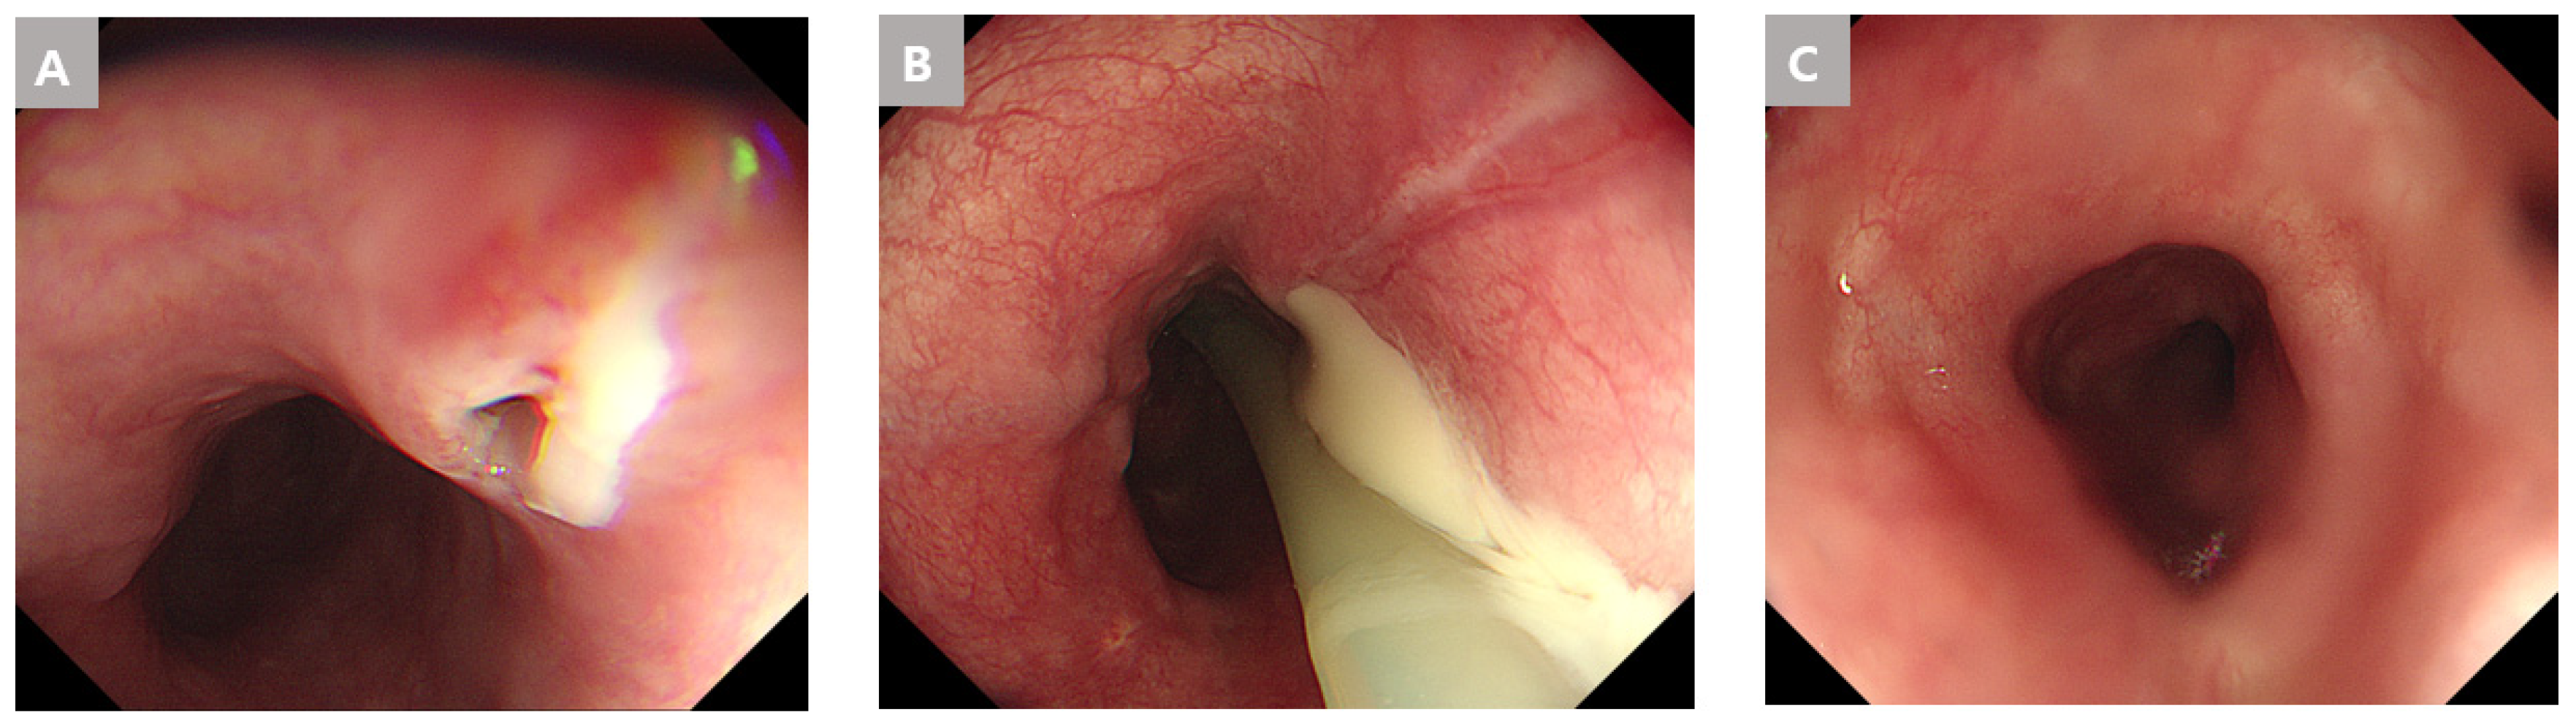

An endoscopy showed diffuse swelling with a small opening discharging pus in the upper esophagus at 23 cm of the upper incisor (UI). The swelling of the esophagus and the gastric cardia were caused by submucosal pus accumulation. A dual knife (Olympus, Tokyo, Japan) was used for the periesophageal abscess drainage, and the mucosal bridge between the true and false lumens from the upper to lower esophagus was endoscopically transected approximately 3 cm vertically. Abscess drainage was confirmed (Figure 2). The drained pus was cultured and stained, but the results were negative.

Figure 2. Endoscopic findings of the esophageal abscess due to an esophageal fish bone foreign body in Case 1. (A) A mucosal protrusion with a small ulcer was observed with endoscopy. (B,C) Endoscopic dissection of the mucosa and submucosa, using a dual knife. (DF) Entirely exposed submucosal layer and drainage of the abscess.